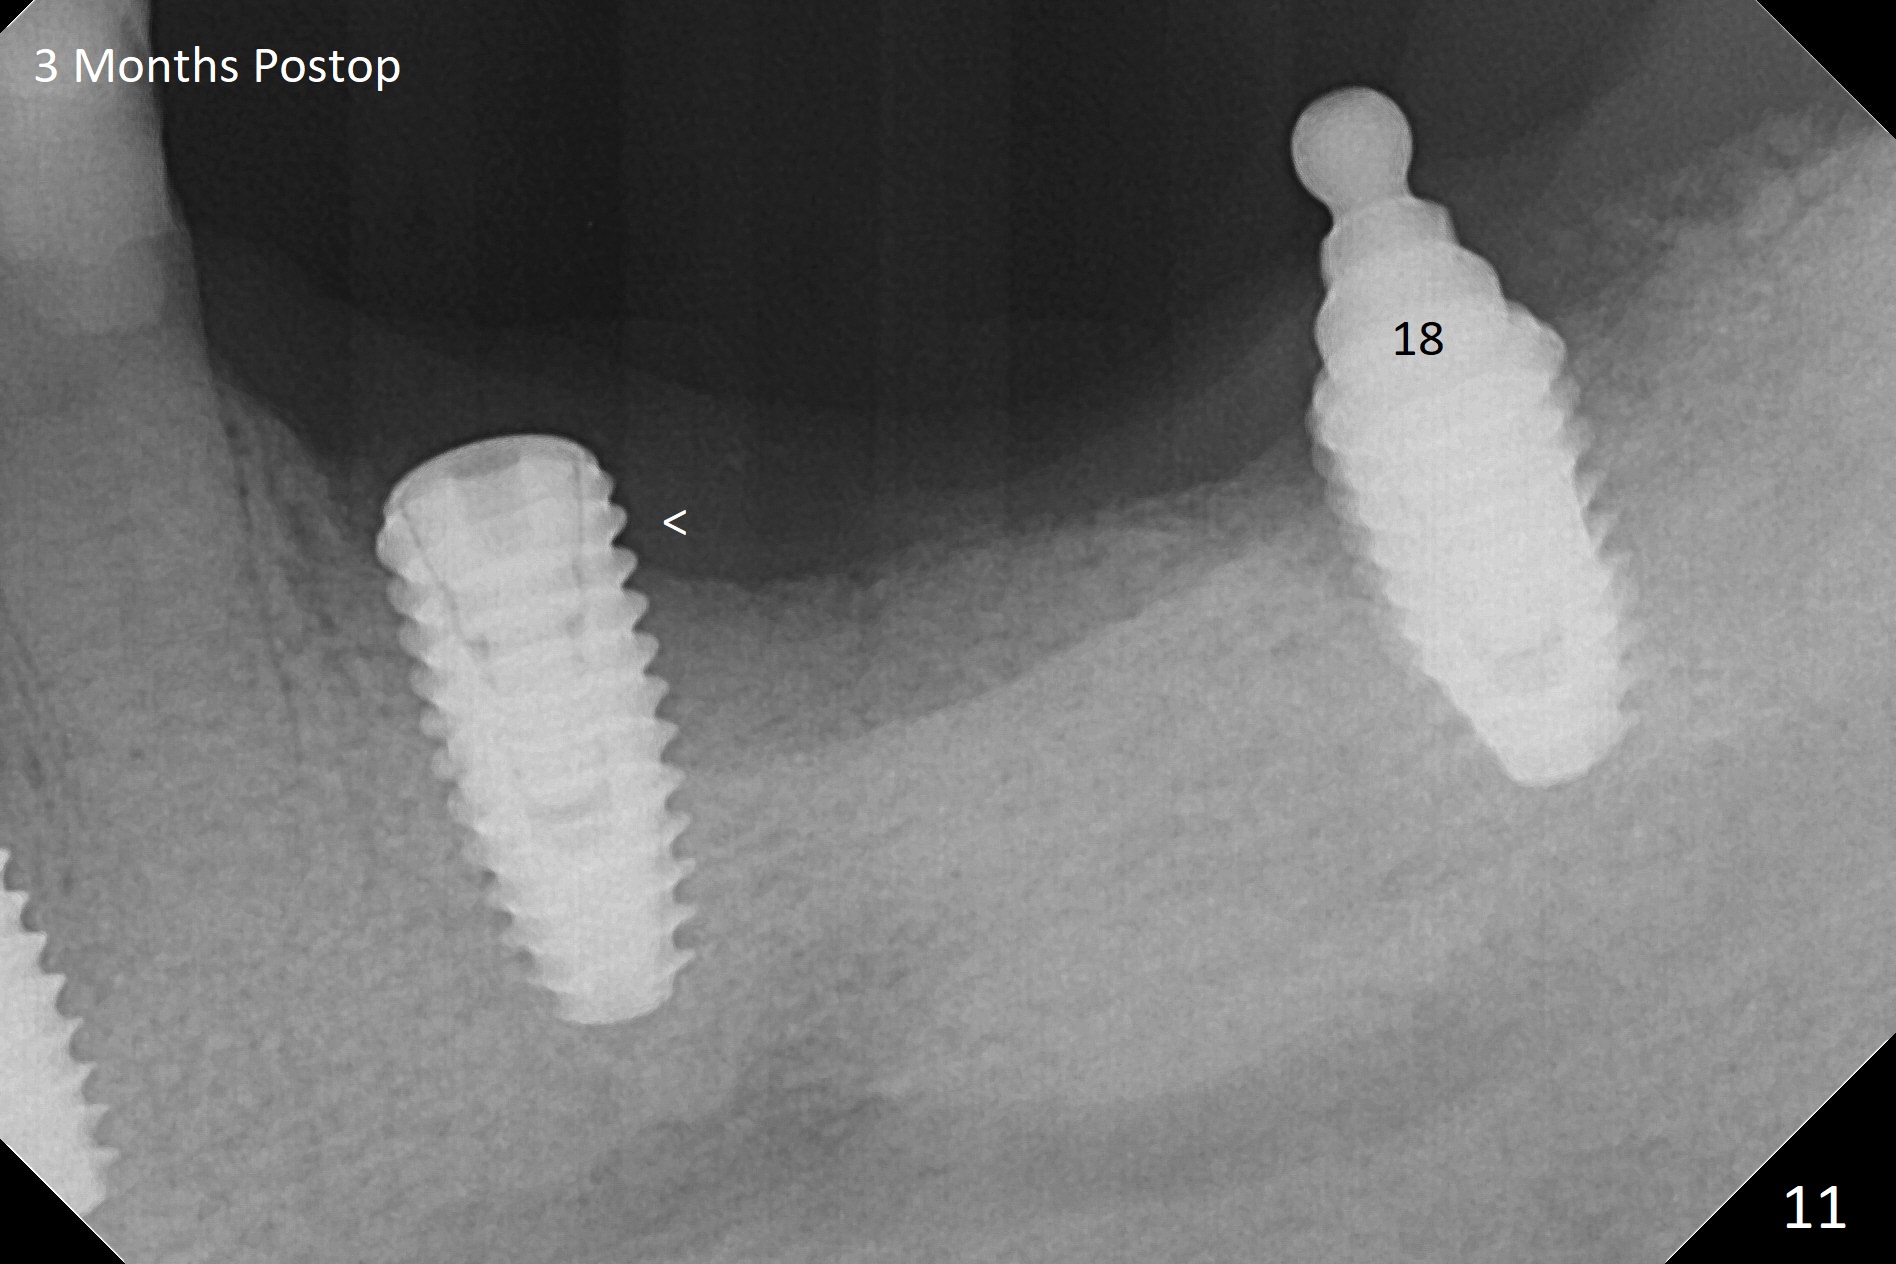

Three months post socket preservation (with buccal plate loss previously), a 3.5x11.5 mm implant is placed at #27 subcrestal (Fig.1). When implants are placed at #22 and 20 (Fig.2,4), threads are exposed buccal (B). Mixture of autogenous bone and allograft is placed to cover the exposed threads (Fig.3,5) following deep placement at #20. For safety, the implant at #20 is buried. Pain control at #18 is poor when initial osteotomy is being established (Fig.6 *), as related to severe infection. Repeated block anesthesia allows to finish implant placement with primary stability; a 3.5x2 mm ball abutment is placed (Fig.7). With placement of 2 other ball abutments at #27 and 22 (Fig.3), the lower existing RPD is converted to a removable provisional (Fig.8). With addition of acrylic, the socket of #20 is covered (Fig.9). There is no apparent bone #20 distal 3 months postop (Fig.10,11 <). Re-graft is needed? The implant at #21 appears immediately subgingival 5 months postop (Fig.12 *). The distobuccal threads are exposed (Fig.13). After decortication, allograft is placed, followed by 6-month membrane. In fact, a shorter and smaller implant should be placed instead. The patient has to wear the RPD for mastication. It would be more painful without it. Later the tissue surface of the RPD is trimmed.